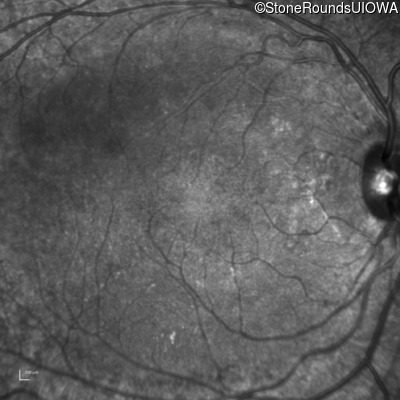

Infrared Fundus Photograph - Left - 20/20 -1

Exemplar